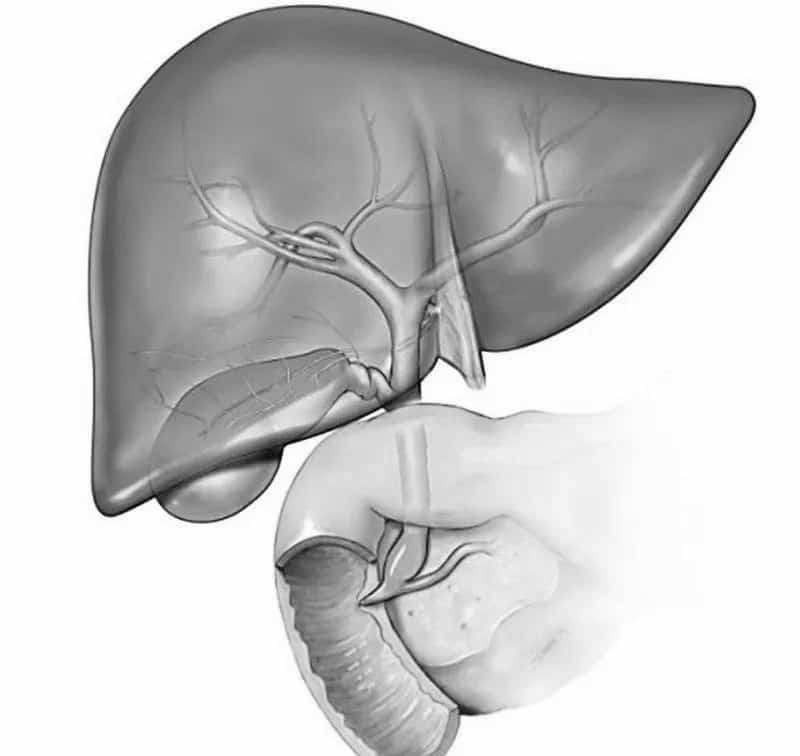

Анатомия и особенности Гартманова кармана желчного пузыря